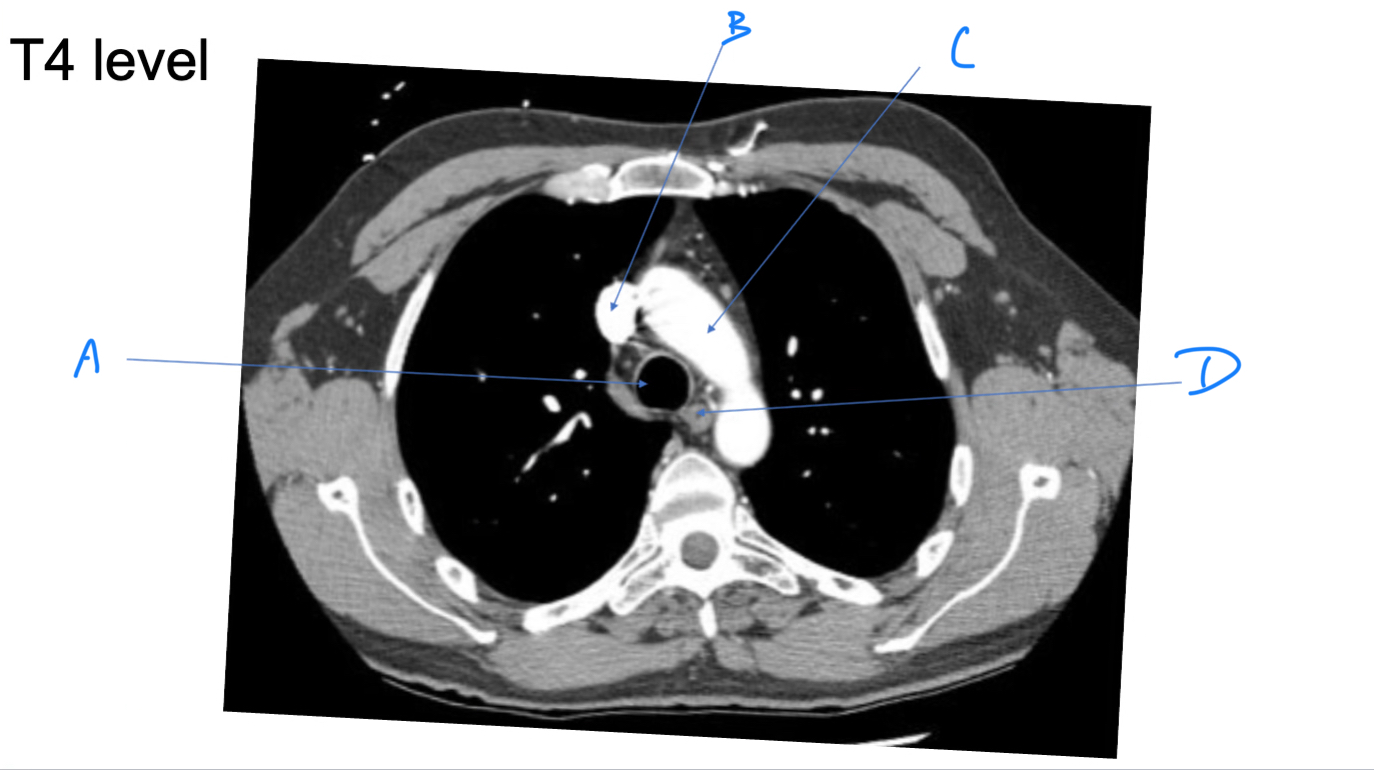

External intercosal m.

A. Identify

Costochondral joint

B. Identify

Internal intercostal m.

C. Identify

Internal thoracic (mammary) a.

A. Identify

Superior epigastric a.

B. Identify

Musculophrenic a.

D. Identify

External intercostal m.

C. Identify

T4

Which DRG was originally infected in a case of shingles involving a horizontal strip of skin that intersects the nipple?